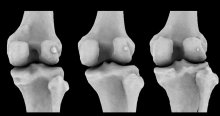

CT scan of two knees with the tiny fabella bones visible

From 1918 to 2018, the number of human knees donning seemingly useless fabellae – small bones buried in the tendon behind some knees – trebled.

Latin for “little bean”, it's linked to knee pain, arthritis, and problematic knee surgeries.